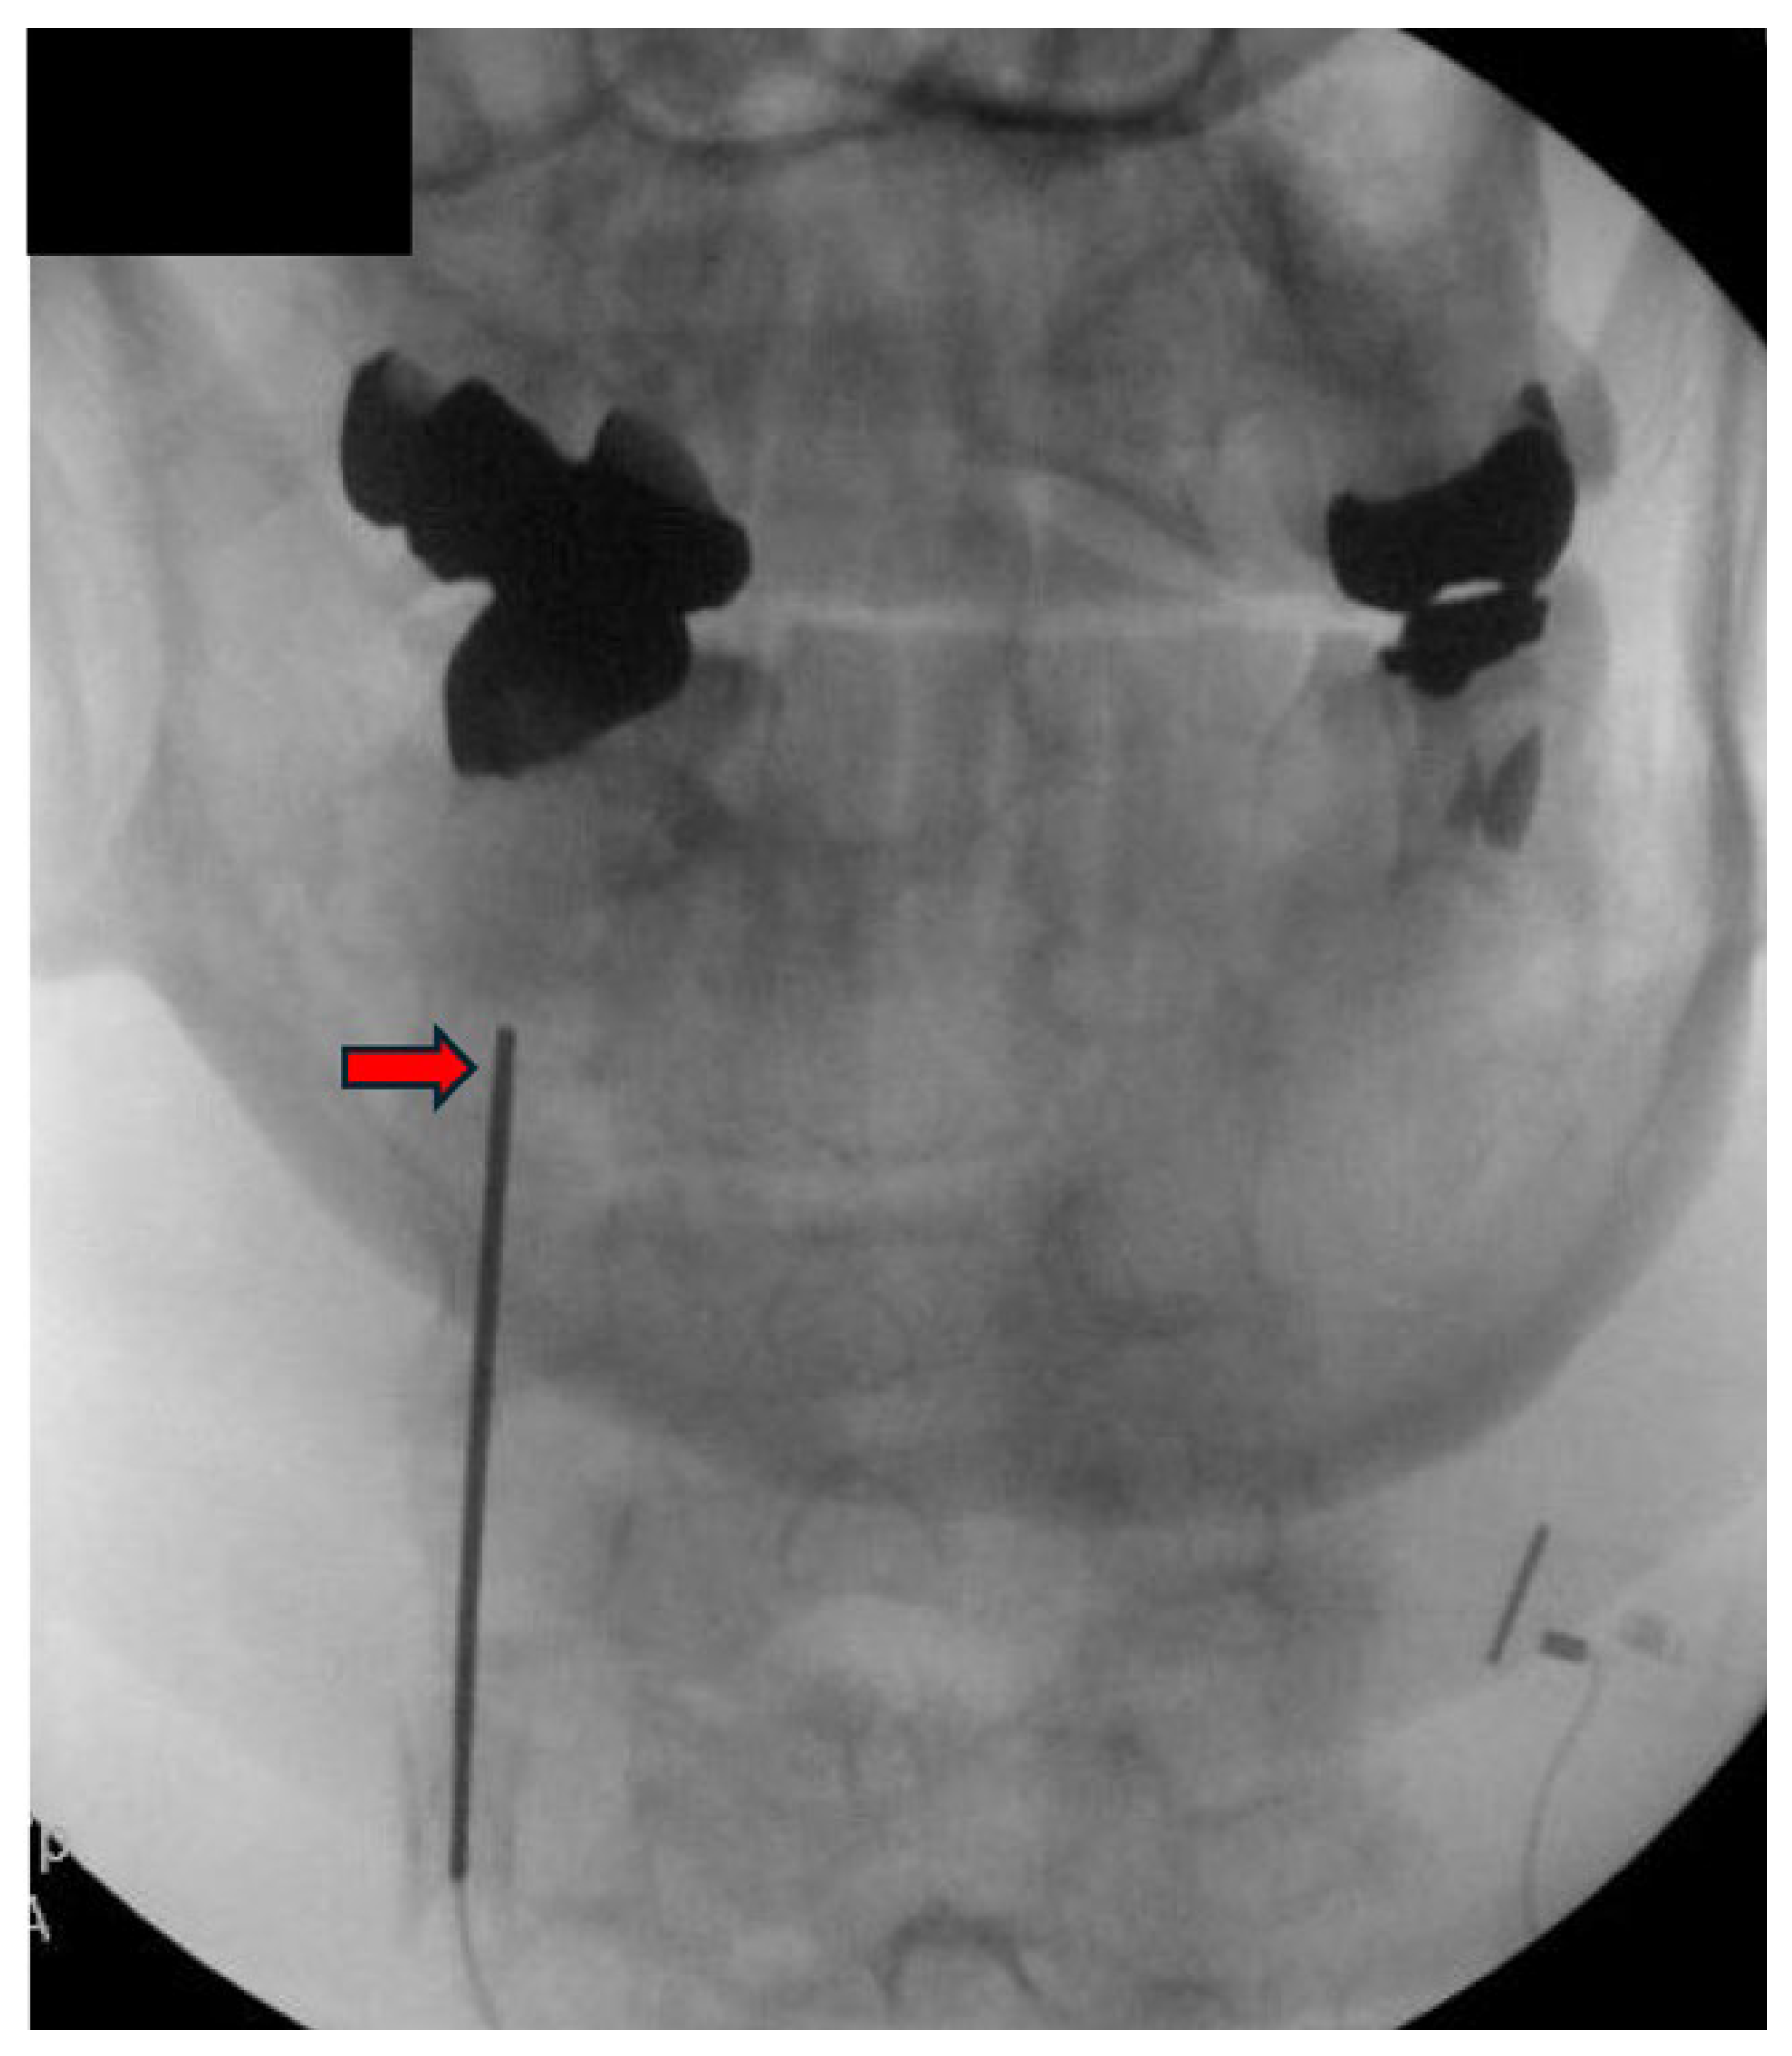

3.3. Procedure Description